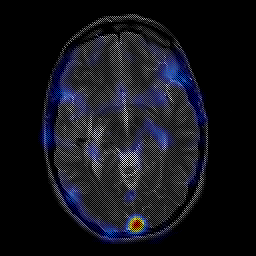

overlay -- Slice #12

[Home][Help][Clinical] Slice 12